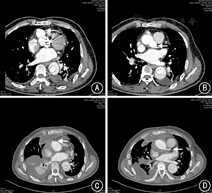

6例患者平均体外循环时间(107±17)min,阻断时间(14±5)min。所有患者无术后并发症发生,均顺利康复出院,平均术后随访24(12~60)个月,术后复查主动脉CTA,冠状动脉开口恢复正常形态,残余瘤体完全消失("金鱼眼"征消失,图1)。